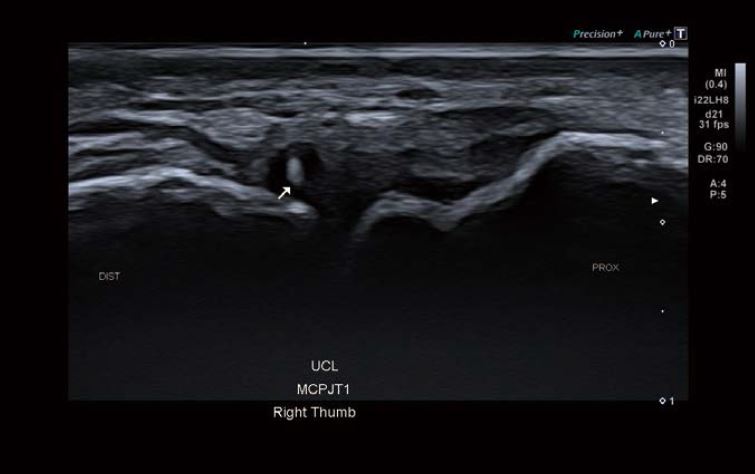

Зображення 2 Візуалізація ЛКЗ показує ехогенну ділянку в дистальному відділі зв'язки. Результати вказують на частковий розрив.